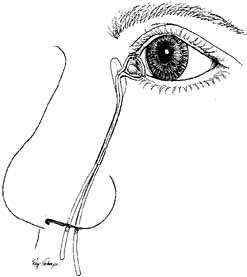

is aided by irrigation with 0.5 mL of an antibiotic steroid solution.  Fig. 19 Probing and irrigation of the nasolacrimal system. Hydraulic pressure is

used in an attempt to force fluid through the obstruction at the valve

of Hasner. If this attempt is unsuccessful, the cannula is slipped

down to the point of obstruction and pushed through gently but firmly. Dye

is injected from the syringe, and the patency of the system is confirmed

by suctioning the dye from the inferior meatus with a soft pediatric-size

plastic suction catheter. Fig. 19 Probing and irrigation of the nasolacrimal system. Hydraulic pressure is

used in an attempt to force fluid through the obstruction at the valve

of Hasner. If this attempt is unsuccessful, the cannula is slipped

down to the point of obstruction and pushed through gently but firmly. Dye

is injected from the syringe, and the patency of the system is confirmed

by suctioning the dye from the inferior meatus with a soft pediatric-size

plastic suction catheter.